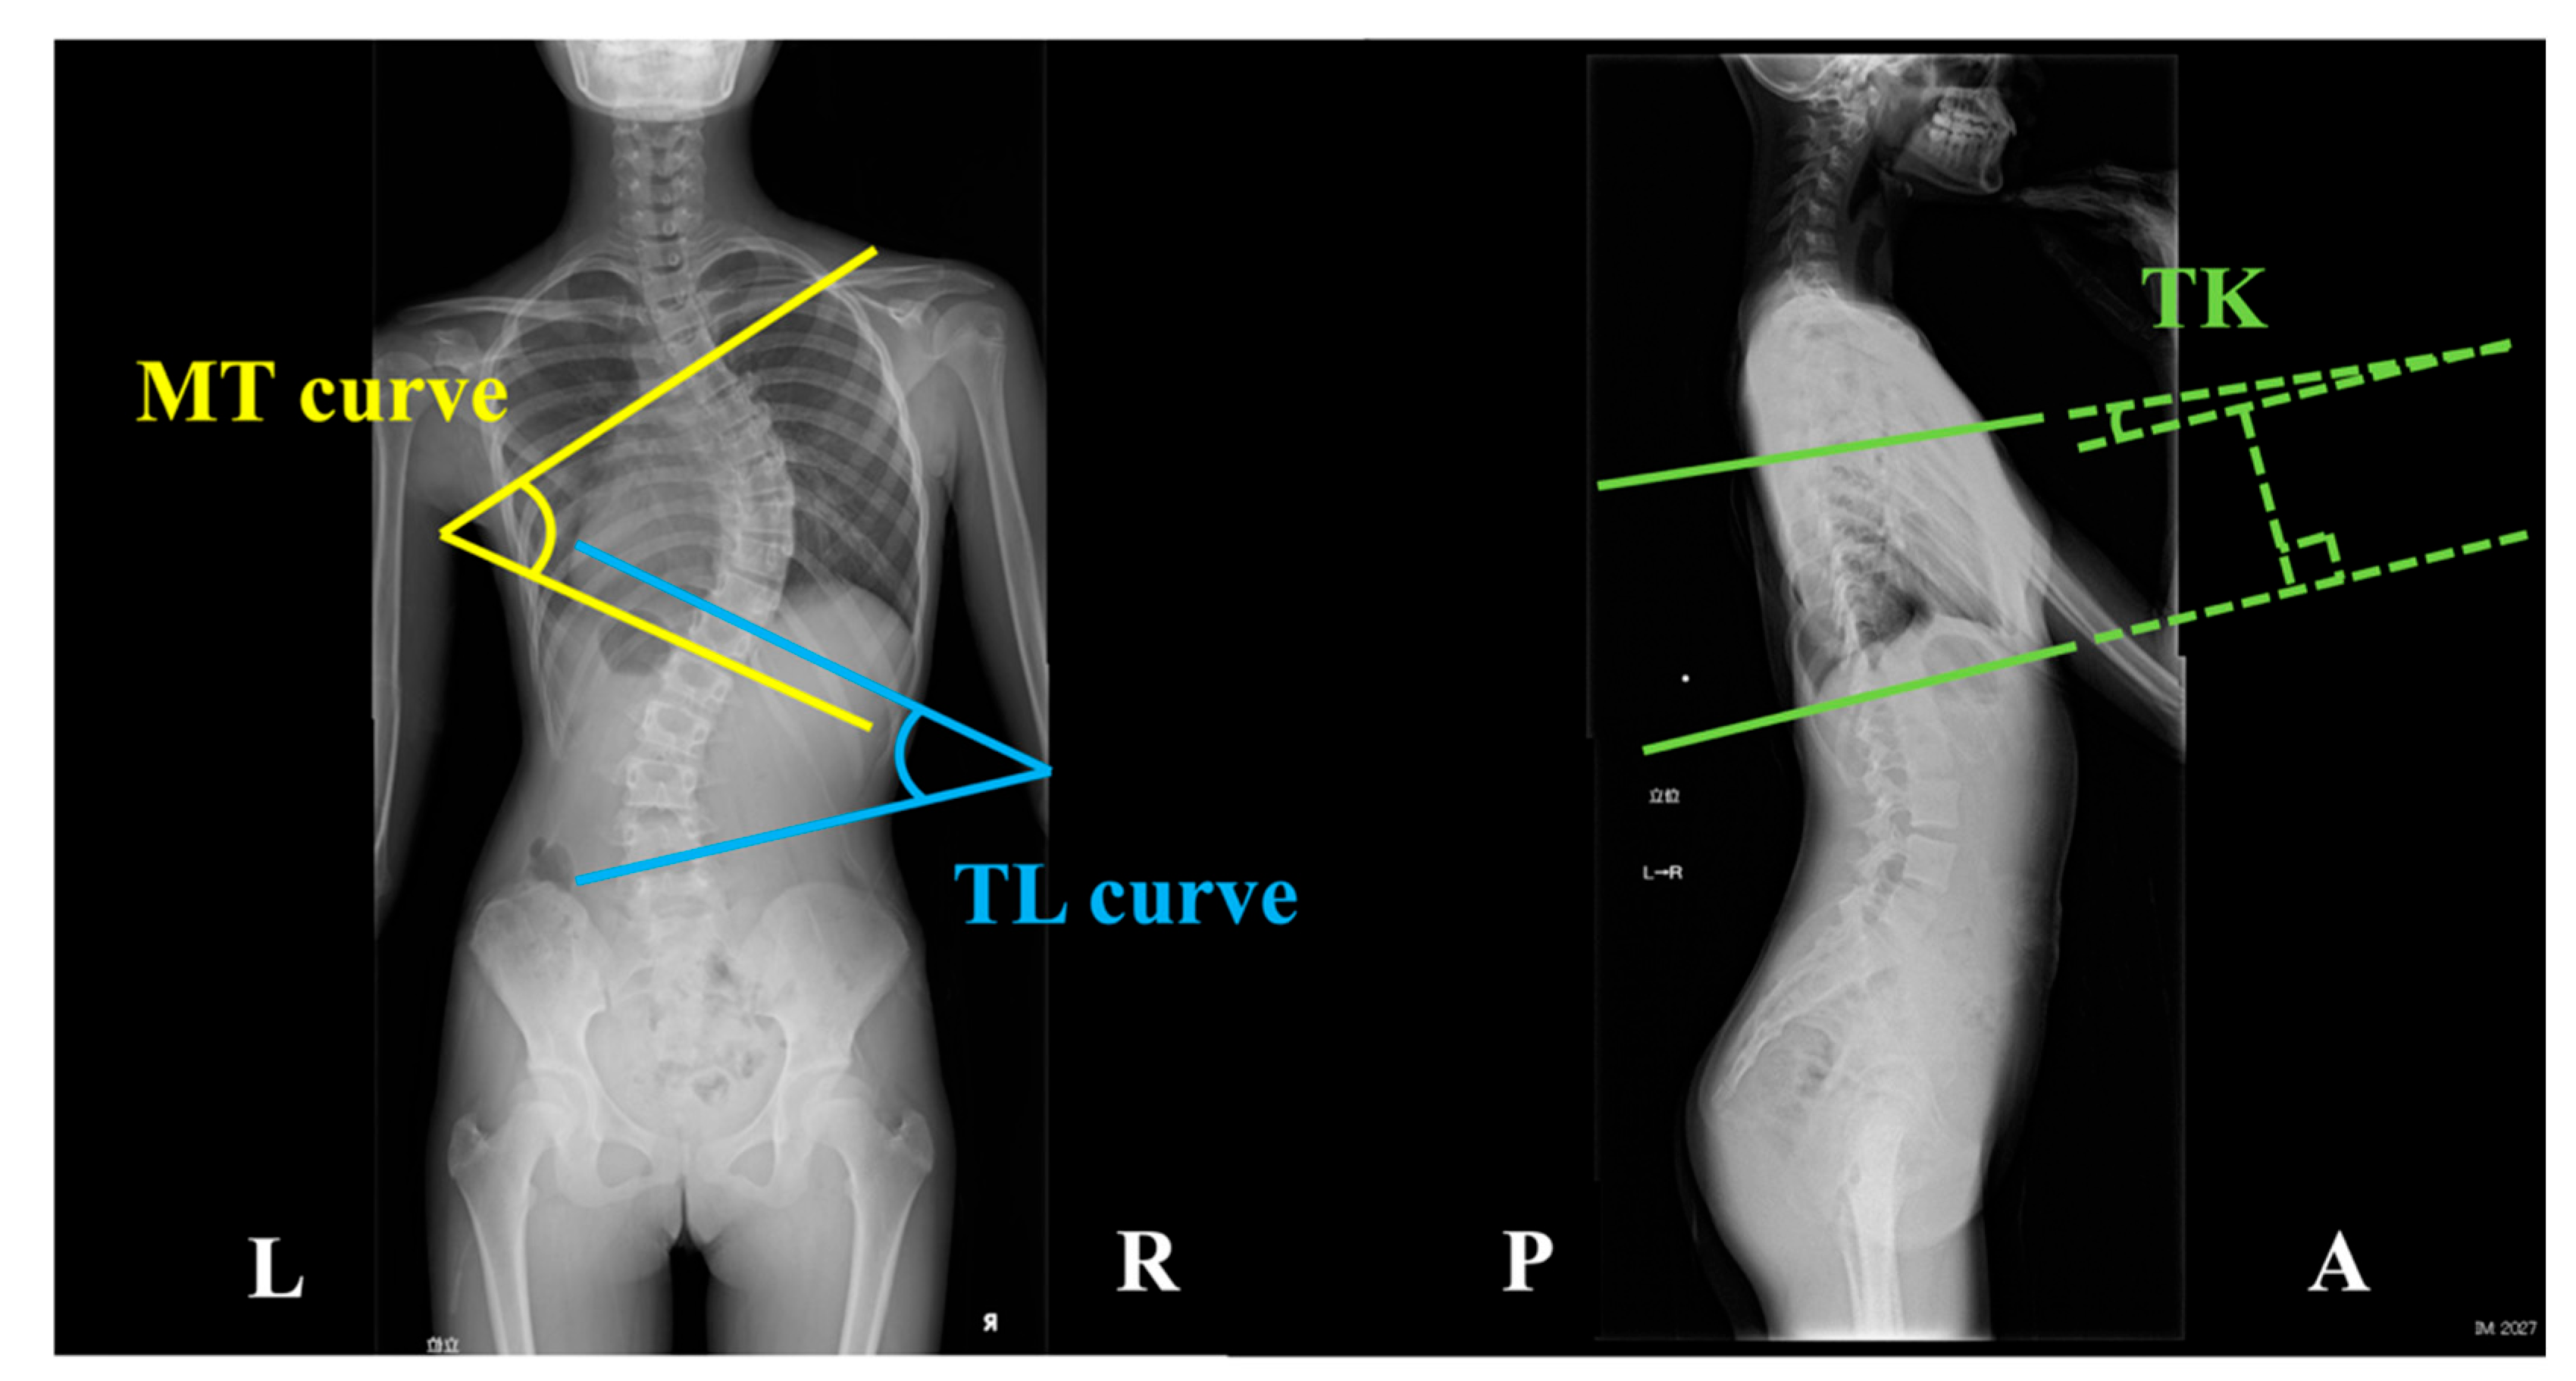

2.2. Spinal Morphometry Using X-ray Imaging

| Main thoracic curve (degree) | 39.1 ± 10.1 |

| Thoracolumbar curve (degree) | 33.8 ± 10.7 |

| Thoracic kyphosis (degree) | 12.6 ± 9.2 |